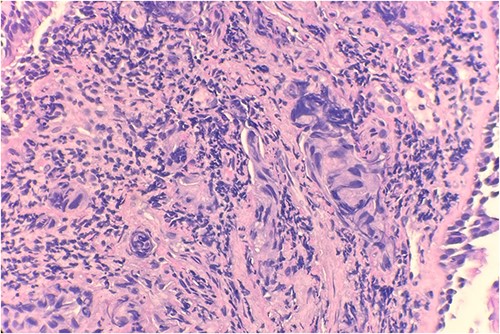

Pathology evaluation from the right middle lobe biopsy showed few clusters of malignant cells, consistent with ADC (Fig. 1). Immunohistochemical staining showed tumor cells were positive for AE1/3, Napsin A and TTF1 (Fig. 2), with ⁓60% Ki-67 positivity. Tumor cells were also negative for CK7 (Fig. 3), p40, p63, CK20 and CK5/6. The overall tumor morphology features and immunoprofile favored moderately differentiated ADC of the lung. However, other primary sites could not be ruled out.

Microscopic examination reveals clusters of tumor cells below the endobronchial lining. Hematoxylin and Eosin (H&E) 40×.